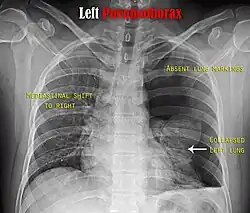

Chest X-ray

A plain chest radiograph, ideally with the X-ray beams being projected from the back (posteroanterior, or "PA"), and during maximal inspiration (holding one's breath), is the most appropriate first investigation.[35] It is not believed that routinely taking images during expiration would confer any benefit.[36] Still, they may be useful in the detection of a pneumothorax when clinical suspicion is high but yet an inspiratory radiograph appears normal.[37] Also, if the PA X-ray does not show a pneumothorax but there is a strong suspicion of one, lateral X-rays (with beams projecting from the side) may be performed, but this is not routine practice.[18][22]

It is not unusual for the mediastinum (the structure between the lungs that contains the heart, great blood vessels, and large airways) to be shifted away from the affected lung due to the pressure differences. This is not equivalent to a tension pneumothorax, which is determined mainly by the constellation of symptoms, hypoxia, and shock.[16]

The size of the pneumothorax (i.e. the volume of air in the pleural space) can be determined with a reasonable degree of accuracy by measuring the distance between the chest wall and the lung. This is relevant to treatment, as smaller pneumothoraces may be managed differently. An air rim of 2 cm means that the pneumothorax occupies about 50% of the hemithorax.[18] British professional guidelines have traditionally stated that the measurement should be performed at the level of the hilum (where blood vessels and airways enter the lung) with 2 cm as the cutoff,[18] while American guidelines state that the measurement should be done at the apex (top) of the lung with 3 cm differentiating between a "small" and a "large" pneumothorax.[38] The latter method may overestimate the size of a pneumothorax if it is located mainly at the apex, which is a common occurrence.[18] The various methods correlate poorly but are the best easily available ways of estimating pneumothorax size.[18][22] CT scanning (see below) can provide a more accurate determination of the size of the pneumothorax, but its routine use in this setting is not recommended.[38]

Not all pneumothoraces are uniform; some only form a pocket of air in a particular place in the chest.[18] Small amounts of fluid may be noted on the chest X-ray (hydropneumothorax); this may be blood (hemopneumothorax).[16] In some cases, the only significant abnormality may be the "deep sulcus sign", in which the normally small space between the chest wall and the diaphragm appears enlarged due to the abnormal presence of fluid.[19]